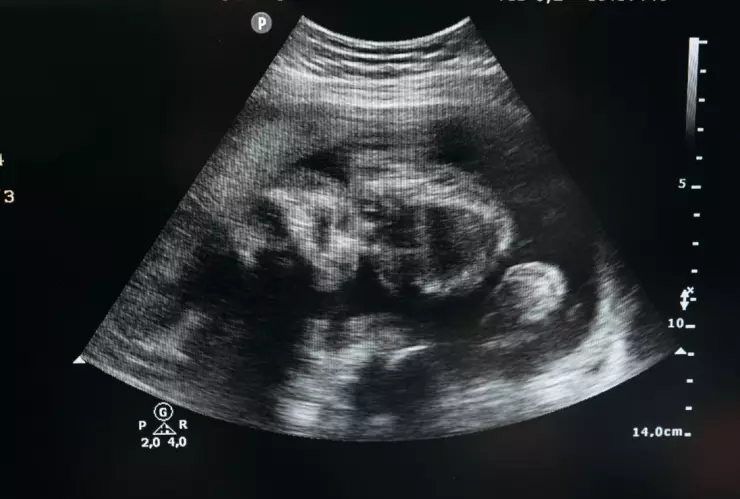

Debido a la emergencia, los doctores advirtieron a los padres de la bebé que tenían que operar. El grupo de especialistas detectó que había un total de ocho fetos dentro de un quiste.

Cada feto medía entre 3 y 5 centímetros de largo, reportó el Doctor Dr. Mohammed Imran a cargo de la cirugía.

"En el diagnóstico inicial, se encontró un quiste o sustancia tumoral. Estaba situado debajo del diafragma. Decidimos extraerlo mediante una operación, que se realizó el 1 de noviembre. Entonces, descubrimos ocho fetos uno tras otro dentro de la pieza”, informó el médico encargado a la prensa local.